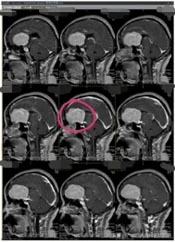

近段时间来,林阿姨头痛越来越重,偶尔还会出现小便失禁,林阿姨这才有所警觉。在医院头颅CT检查,显示:前颅底巨大占位,考虑脑膜瘤可能性大。林阿姨吓坏了,半辈子都平平安安,想不到脑子里居然有这么大的一个肿瘤。

孩子们也非常担忧,通过四处打听,林阿姨来到了广东三九脑科医院。进一步影像检查也提示是:前颅窝底巨大占位性病变,考虑脑膜瘤可能性大。

肿瘤体积巨大,占位明显,医院副院长、神经外五科主任鲁明和团队一起经过讨论,快速制定了安全且风险较小的手术方案,术中需要避开重要血管,尽最大可能全切除肿瘤。术前进行全脑血管造影,影像显示:前颅底异常染色,呈类圆形,肿瘤主要是由右侧脑膜中动脉前支、右侧眼动脉分支参与供血;决定先行肿瘤栓塞术,术后加压包扎送病人至手术室,行“前颅底巨大脑膜瘤切除术”。肿瘤周围血管丰富,已侵犯重要神经;导航准确定位,显微镜下见肿瘤起源于大脑镰及前颅底,阻断肿瘤血供后,先钨刀切除左侧额部部分肿瘤,再超吸切进行瘤内减压,最终镜下将肿瘤切除干净。